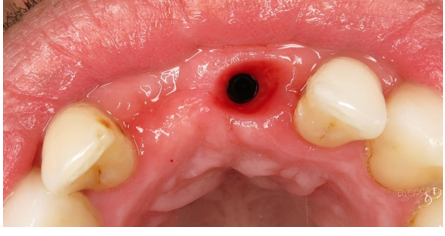

CBCT scan OF UR1 Site, peri-apical cyst?

Extraction of the UR1